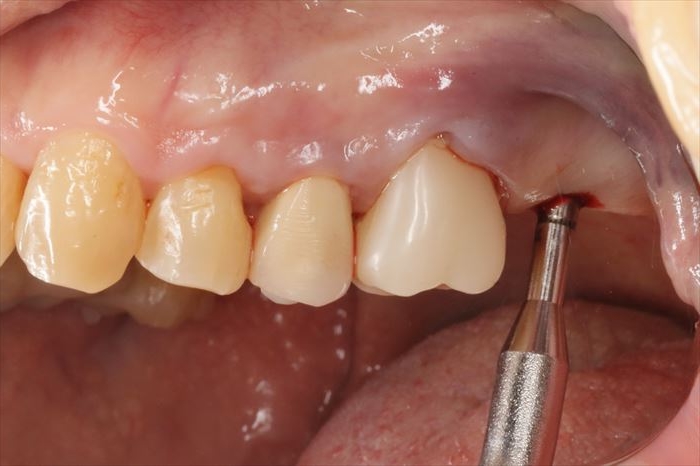

オステオトームで上顎洞底の挙上が出来ましたら、

インプラント床(しょう:インプラントを植えるための穴)を顕微鏡で覗いて、

空気の漏れや上顎洞の粘液の湧き出しが無いことを確認します。